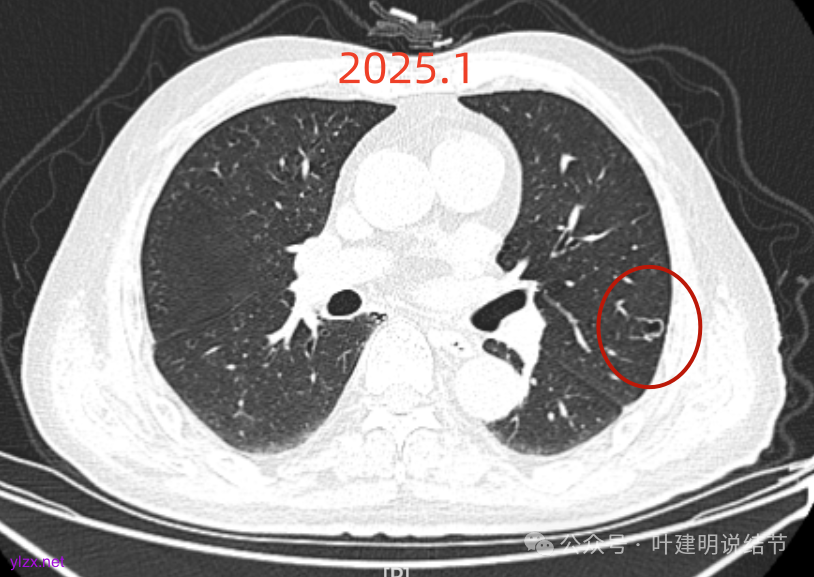

先来看2025年1月的影像:

右下叶也有囊腔灶。

两肺其他地方多处肺大泡。

左肺上叶红色这处是囊腔型病灶,囊壁略不均,似有微小血管进入囊壁,对比2023年4月整个囊腔来讲有扩大,需要考虑囊腔型肺癌的可能性大。右侧蓝色的并不是典型囊腔型肺癌的表现,再加上两肺绿色这些慢支肺气肿与肺大泡的影像,右侧的就更加不确切,至少近期不能够考虑右侧也要开刀的事情。其实左侧的主病灶相对于其他表现更典型的囊腔型肺癌来说,由于囊壁密度偏高,也不是百分百必定是肺癌。我的想法还是先等脑梗情况稳定,并且间隔4~6个月复查病灶再有进展在考虑单孔胸腔镜下局部切除就可以。淋巴结可以考虑采样,但一般不至于阳性。破是不会切破的。消融不建议,囊腔灶更难通过穿刺获得病理依据,况且东西在边上,能局部楔切,当然首选手术。意见供参考!